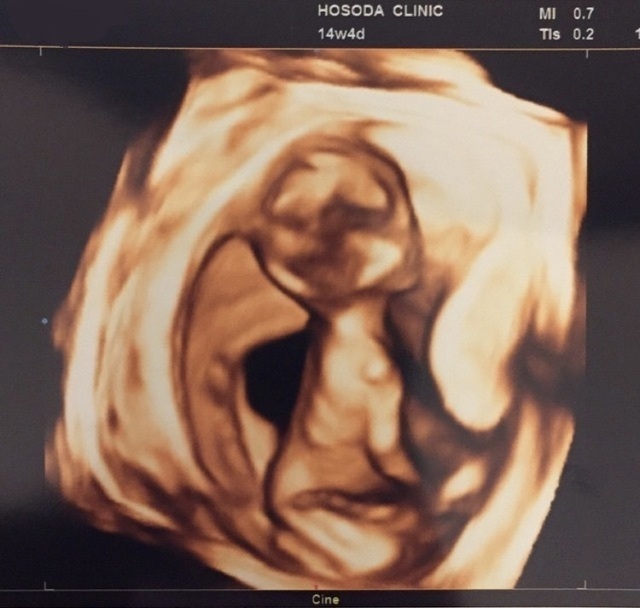

14週0日(14w0d・性別不明)|きなこもっち- さん(32歳)

エコー写真撮影時のエピソード:

病院の都合で、急な転院が決まり転院先で初めてのエコー写真です。新しい病院では、エコーが3Dで見ることができ、立体的な我が子の様子を初めてみて、また動く様子もハッキリと見られてうれしく思ったのを覚えています!

お姉ちゃんになる娘は、まだ分からないようですが、なんとなく感じているのか時々お腹に顔を当てています。まるで、指しゃぶりをしているようなお腹の中の我が子♪早く会いたいです!